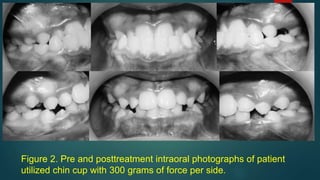

Figure 1. Pre and posttreatment intraoral photographs of patient utilized

chin cup with 600 grams of force per side.

Figure 2. Pre and posttreatment intraoral photographs of patient

utilized chin cup with 300 grams of force per side.